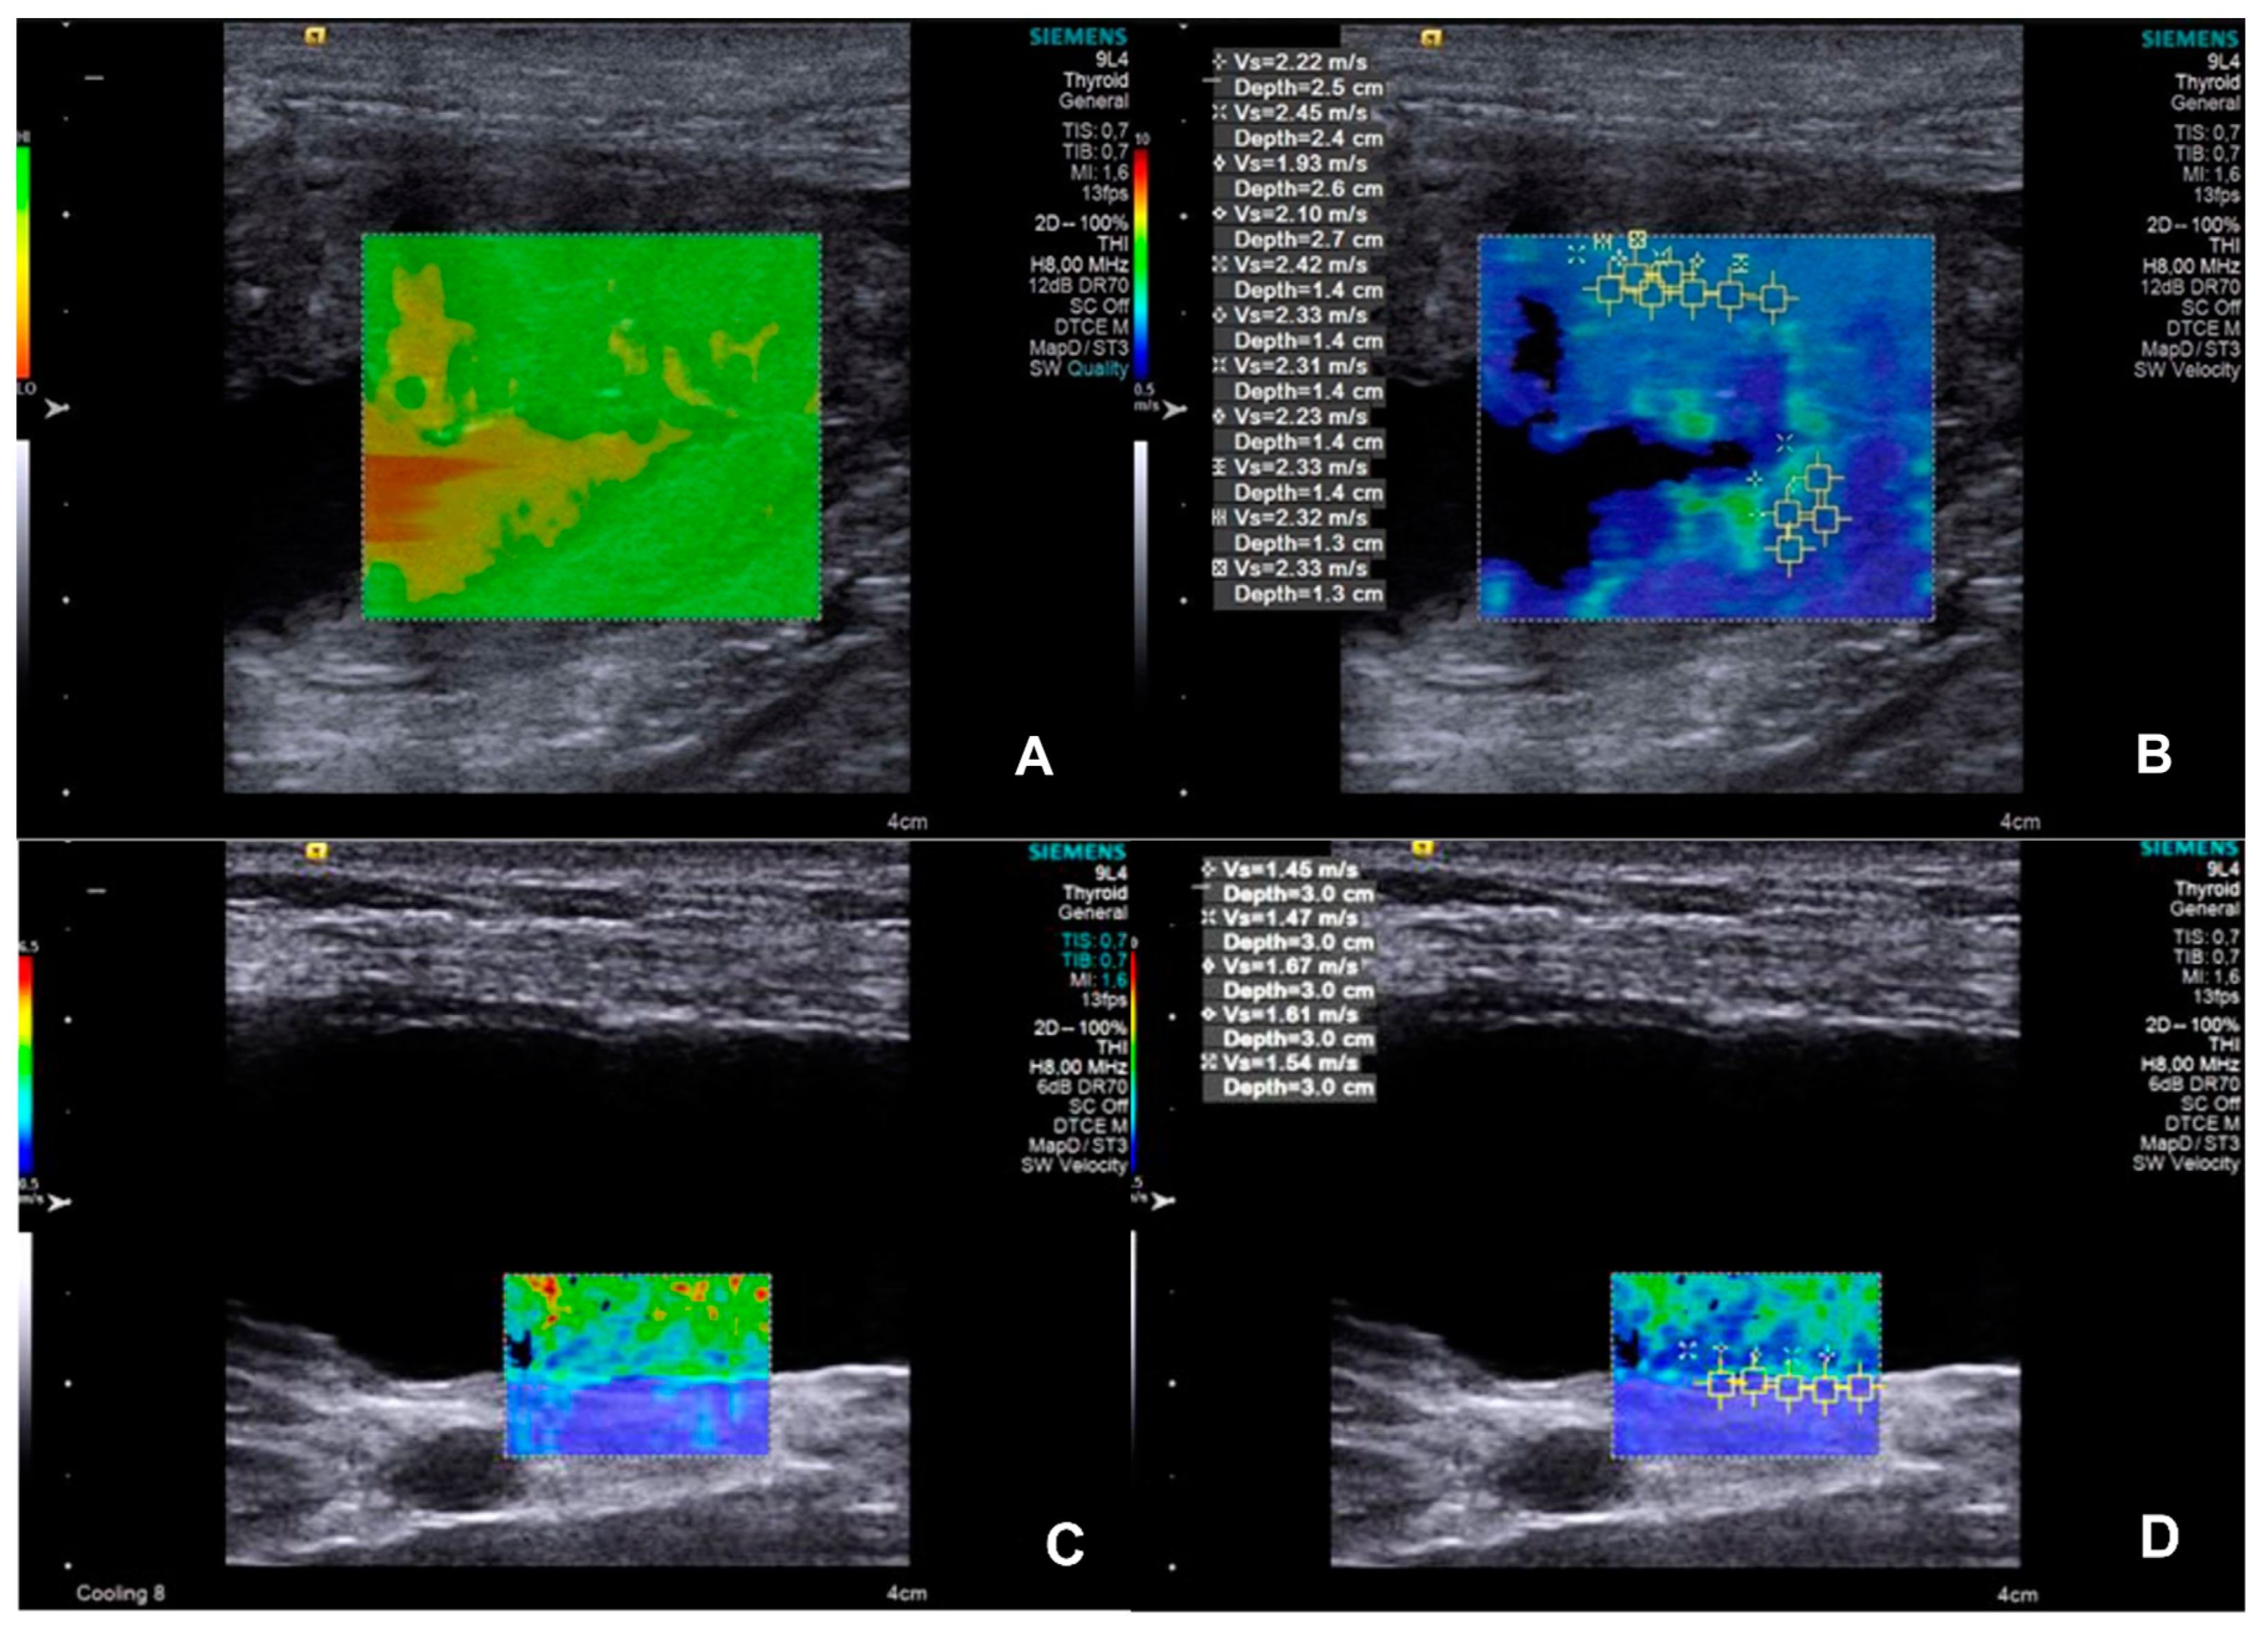

| Variable | Group | Median±IQR | P-value | Cut-off value |

| SWV of the bladder wall (m/s) | CON | 1,41±0,50 | 0,0045 | >1,585 |

| UTC | 2,53±2,11 | |||

| Sensitivity (%) | Specificity (%) | Likelihood ratio | AUC | |

| 100,0 | 88,89 | 9,000 | 0,984 | |

| Bladder wall thickness (cm) | Group | Median±IQR | P-value | Cut-off value |

| CON | 0,14±0,26 | 0,0003 | >0,165 | |

| UTC | 0,28±0,05 | |||

| 85,71 | 87,50 | 6,857 | 0,919 |